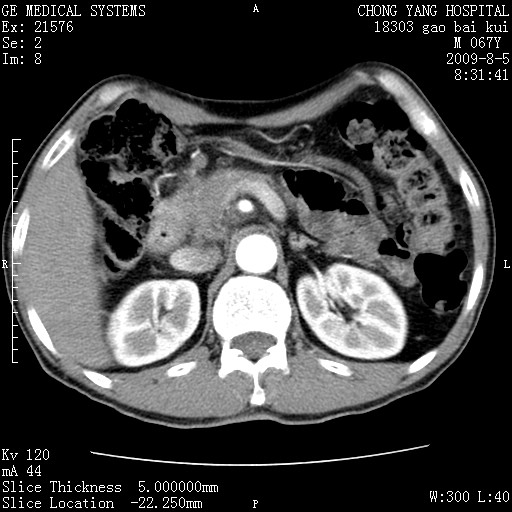

这个也过了,考虑胰腺钩突癌或壶腹癌,不除外胰管粘液乳头瘤伴胰管扩张,肝内胆管积气.

1)考虑胰头癌或壶腹癌并胰管扩张。2)肝外胆管扩张、积气,胆囊影未见;考虑术后改变。3)胃壁增厚?建议必要时行胃镜检查。

虑胰腺钩突癌或壶腹癌,不除外胰管粘液乳头瘤伴胰管扩张,肝内胆管积气.

考虑胰头癌并十二指肠受侵。